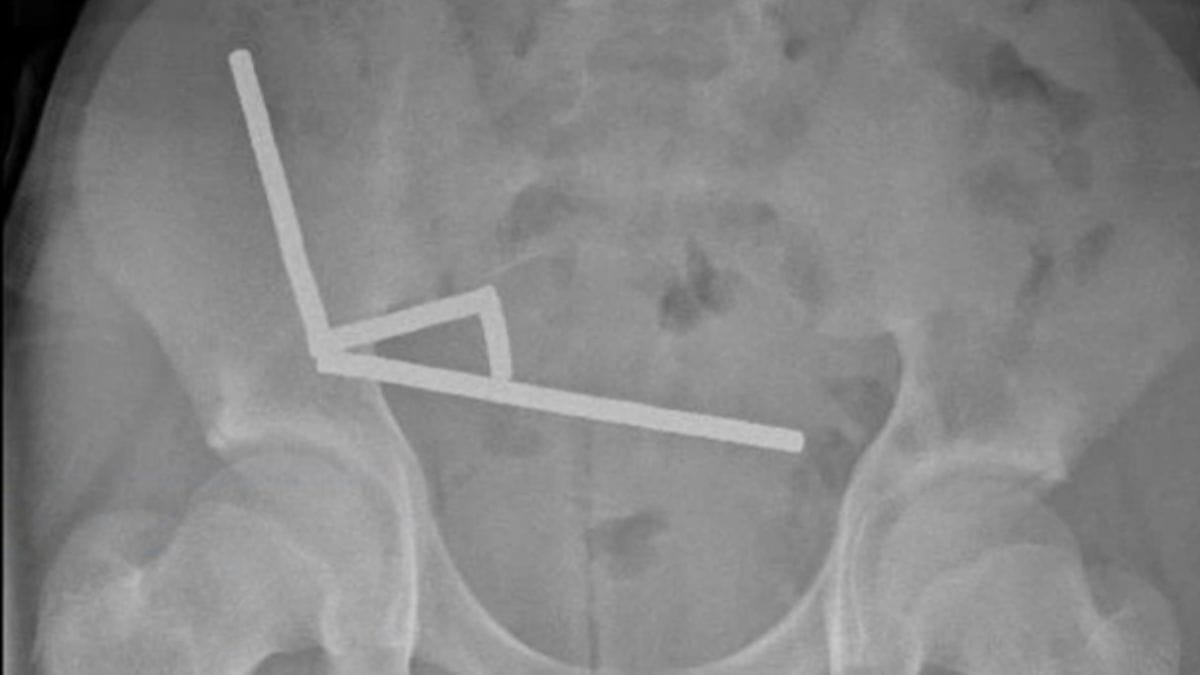

Vaka raporunda paylaşılan röntgen görüntüsü

Yeni Zelanda'da yaşanan tıbbi vakada, 13 yaşındaki bir çocuğun yuttuğu yaklaşık 100 mini neodyum mıknatıs, bağırsak dokusunda ciddi hasara yol açtı. "New Zealand Medical Journal" dergisinde yayımlanan vaka raporuna göre, günler süren karın ağrısı şikayetiyle hastaneye getirilen çocuğun röntgen görüntülerinde, karnının sağ alt bölgesinde birbirine yapışmış metal yığınları tespit edildi.